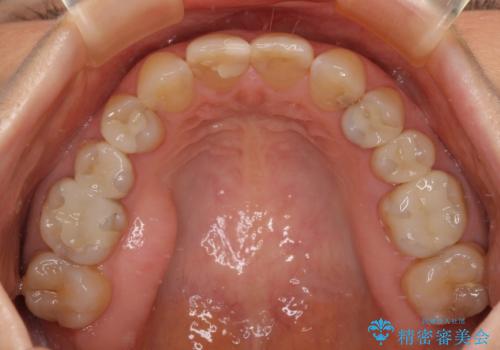

- 上顎2前歯の色を気にして来院された患者様です。

2本ともに虫歯治療による充填材の変色などによりつぎはぎのような前歯となっていたため、オールセラミッククラウンにて補綴治療を行うこととしました。